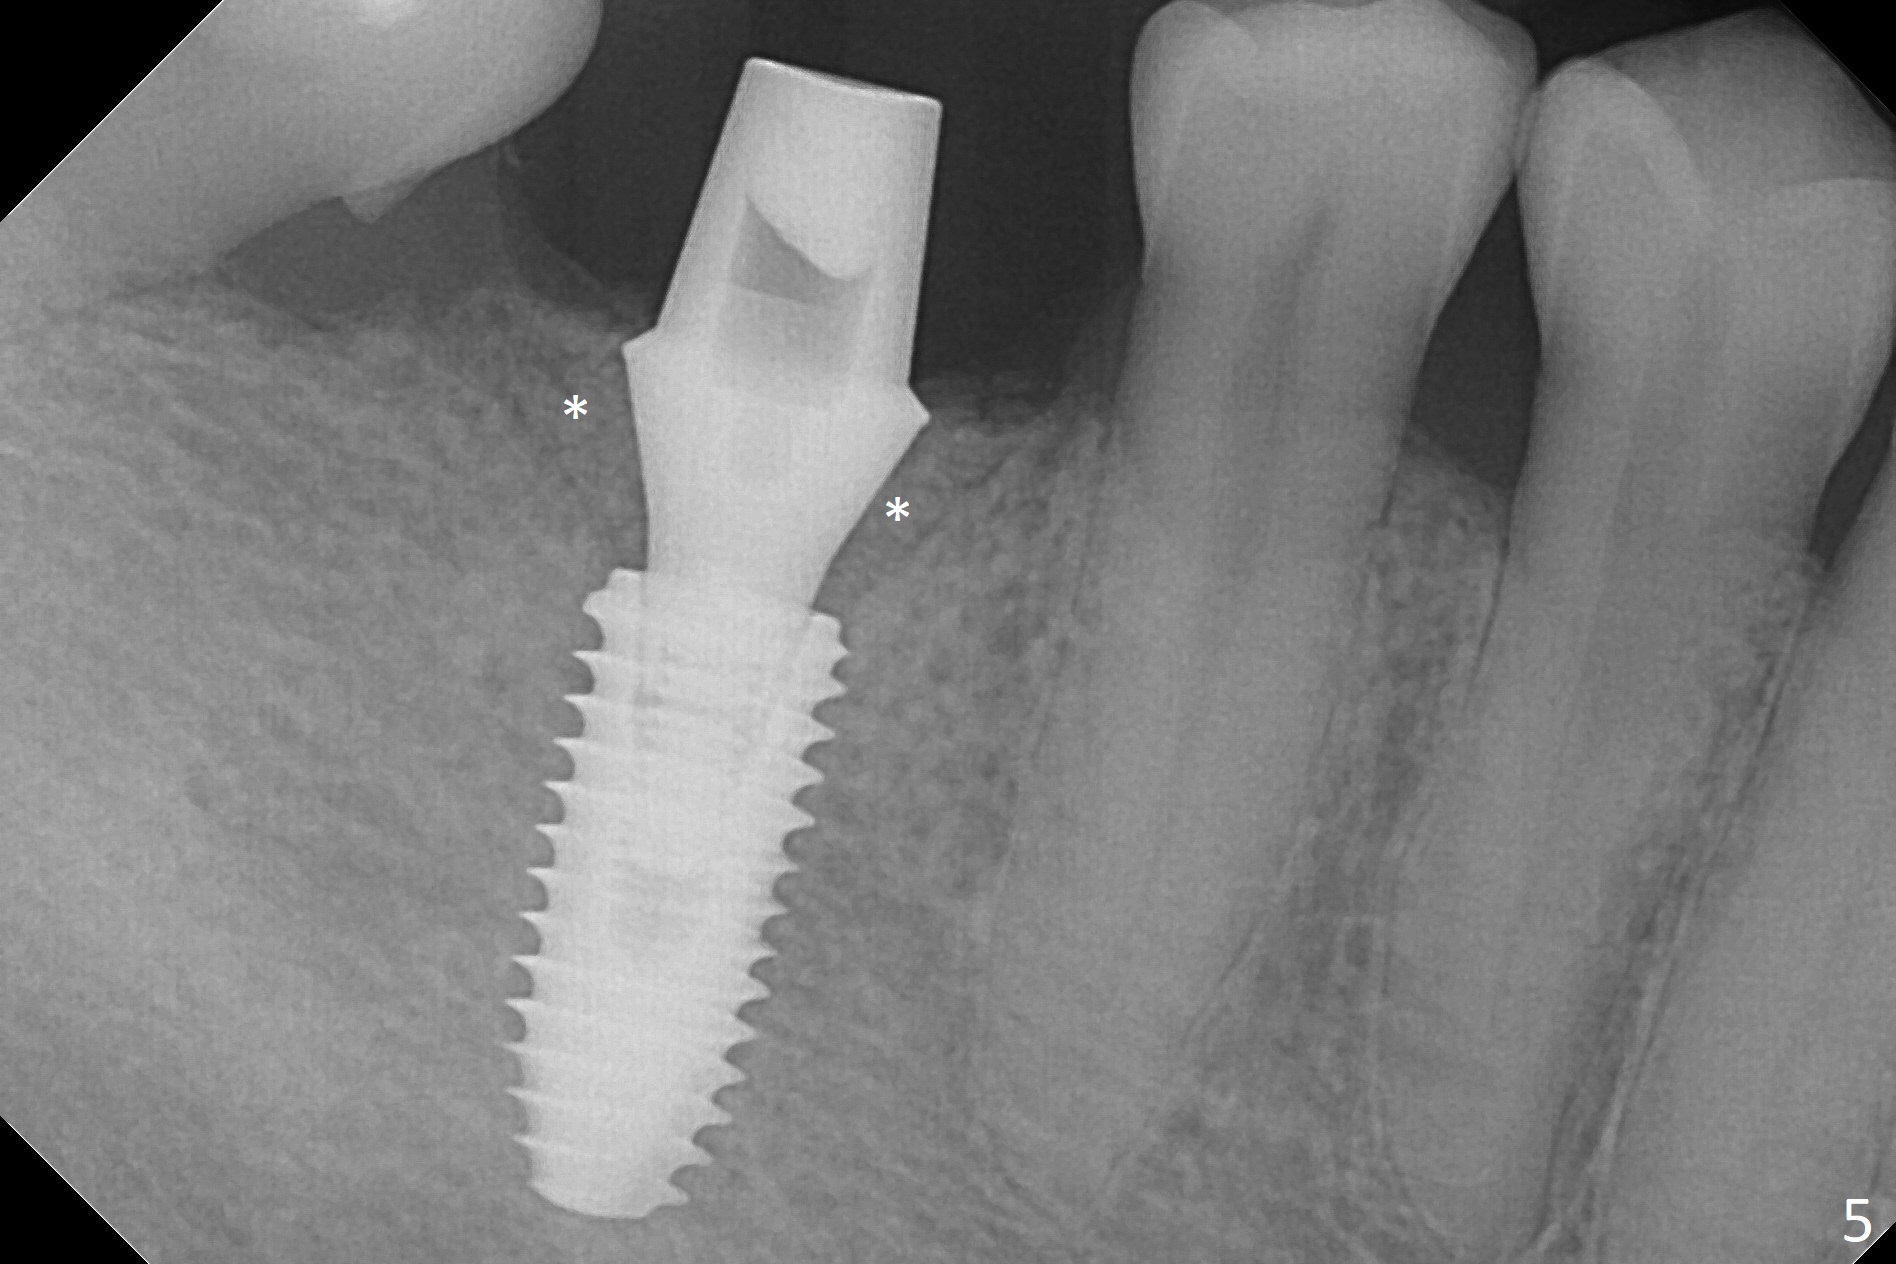

When the residual roots of the tooth #30 (Fig.1) are removed, the buccal crest is found ~ 2 mm apical to the lingual one (Fig.2 <); while the initial depth of osteotomy is 11.5 mm (yellow lines), the parallel pin is 10 mm long. To place a 5x11.5 mm implant at the level of the buccal crest (Fig.4 (>45 Ncm)), subsequent osteotomy depth is 13 mm using the lingual crest as a landmark (Fig.3 (4 mm drill in place)). After insertion of a 5.7x5.5(3) mm abutment, Vanilla Graft is placed (Fig.5 * with 2 mm buccal gap). The abutment with a provisional is loose 4 months postop (Fig.6). The permanent restoration is cemented 6 months postop. The abutment screw is loose and fractured 8 and 11 months post cementation, respectively (Fig.7). The fractured screw seems to be loose within the implant well and is easily re-winded out using Screw Removal Kit (sr-kit.html). When the crown/abutment at #30 is loose 2nd time 1 year 7 months post cementation (Fig.8 taken post retightening), the screw at #19 fractures. The tooth #2 needs a crown. The patient cannot use the anterior teeth, since the teeth #8 and 9 have root fracture. Can extraction and bone graft increase bone height? The screw re-fractures 9 months later (Fig.9). The dislodged crown is sectioned; the abutment is reseated completely (Fig.10) for a new crown. The tooth #2 needs RCT, B-U and crown, while the tooth #1 extraction (Fig.11).